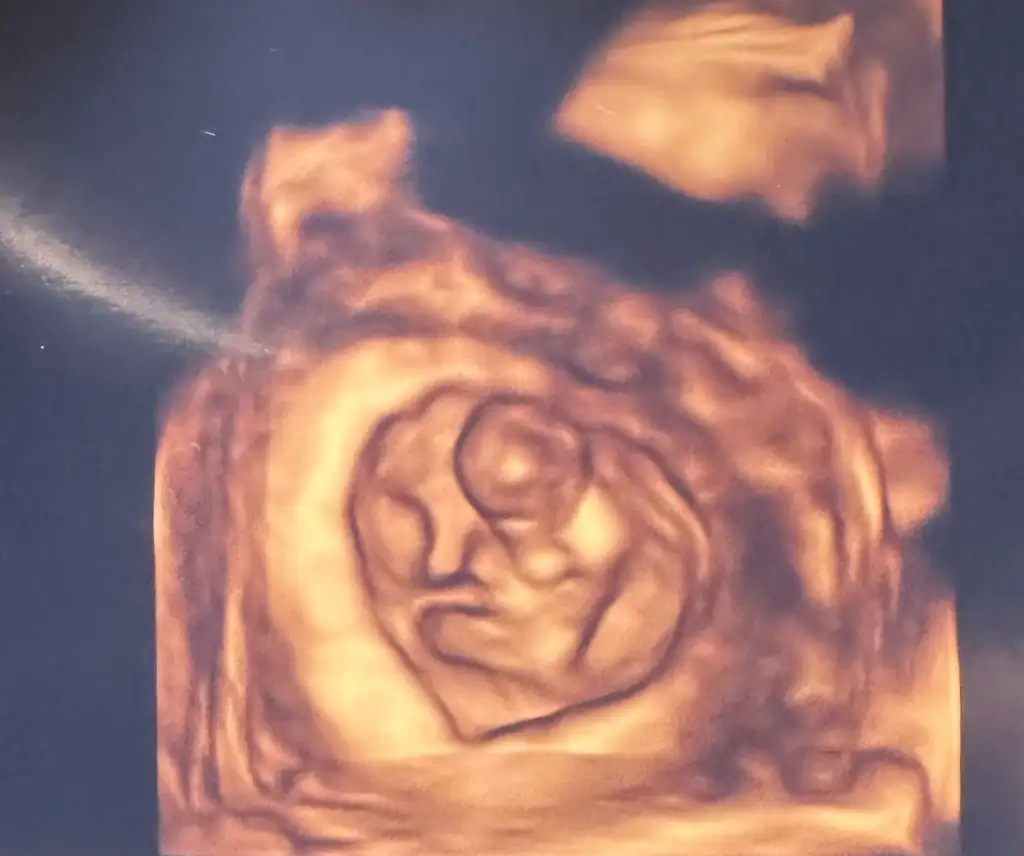

Ben de bir tahmin alabilir miyim minik kurbağam için :) 8+4 idi burada. Biz anne-baba olarak erkek hissediyoruz ama etrafımızdaki herkes kız hissediyor 🫠

Eklentiler

• IMG_7373.webp

IMG_7373.webp

49,2 KB · Görüntüleme: 4